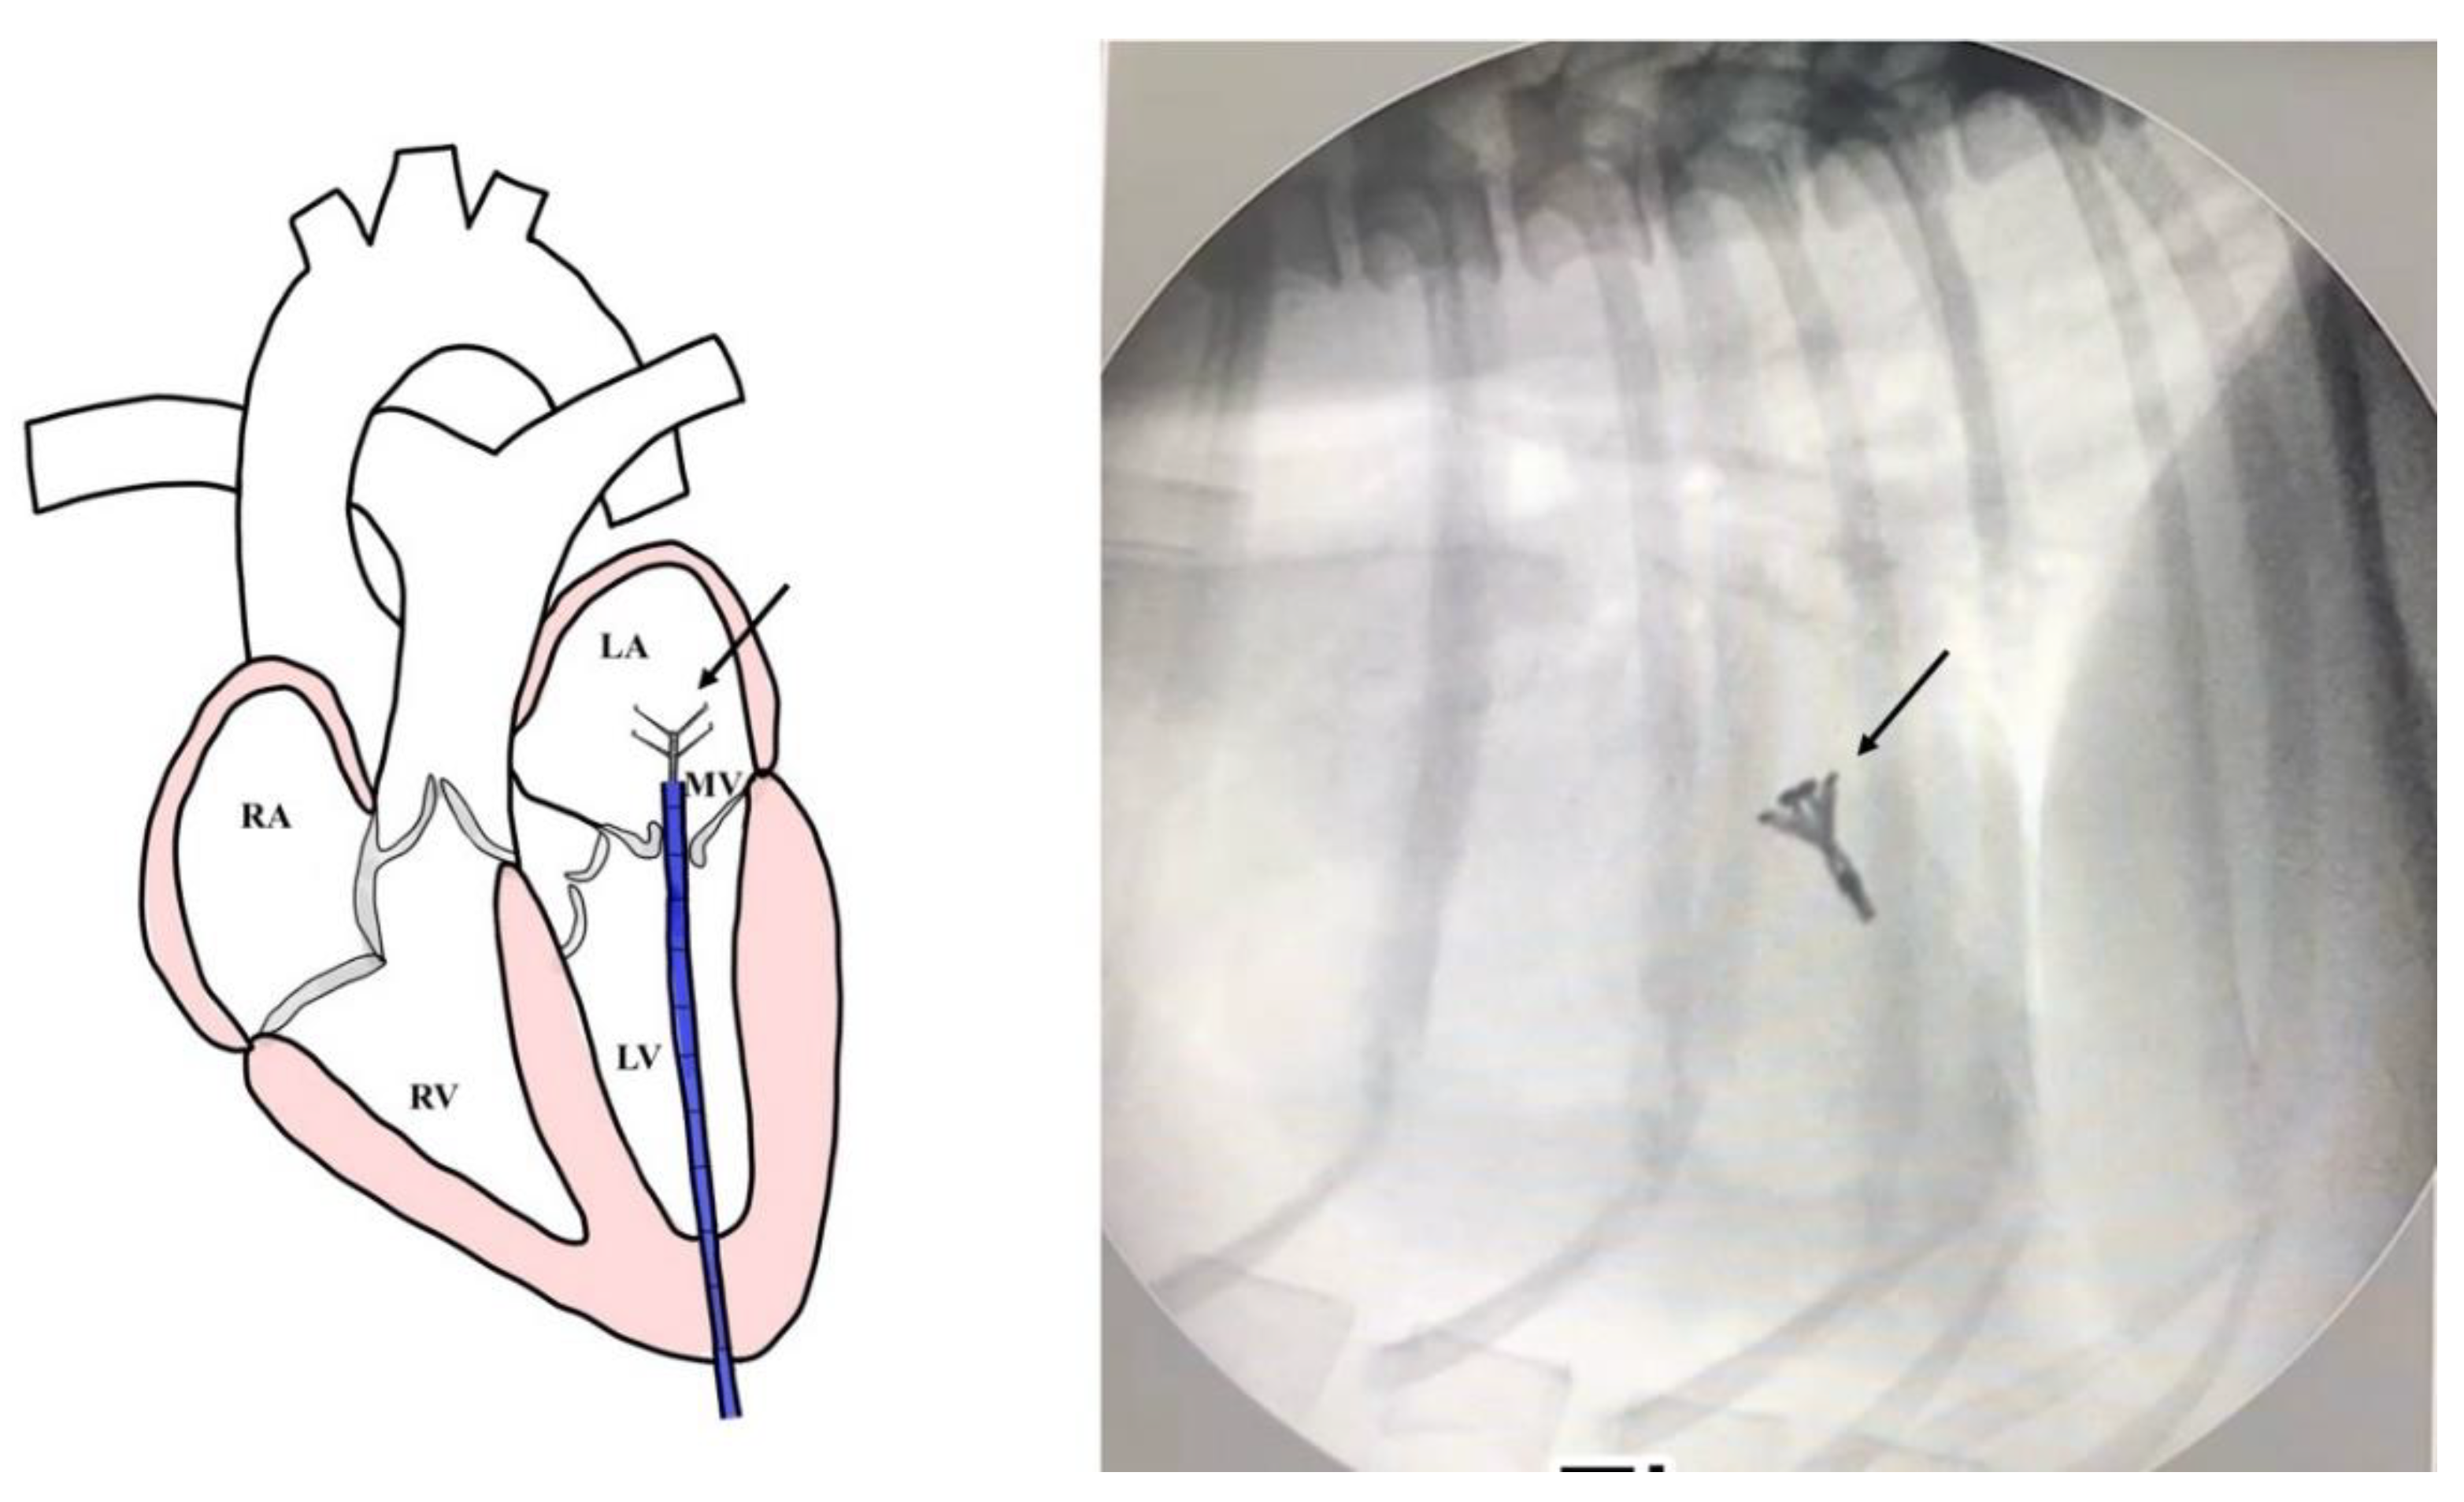

All dogs were assessed for a physical examination (inspection, palpation, percussion, and auscultation), for general health status. In this evaluation, mucous membranes, capillary refill time, rectal temperature, heart rate, heart sounds, pulse rate, and state of hydration were assessed. The dogs presented with a history of coughing, dyspnea, and exercise intolerance. Thoracic radiography revealed left heart enlargement (Figure 1). The mitral valve structure was evaluated by 3D transesophageal echocardiography, and a satisfactory clamp position was confirmed using fluoroscopy and 3D- TEE as shown in Figure 2 and Figure 3.

All radiographs were obtained using a digital radiography system, with dogs positioned in right lateral recumbency, and dorsoventral views. Thoracic radiographic images were captured using a GE Revolution XR/d digital X-ray system, operated at tube potentials from 60 to 130 kVp. The lung field, dilation of the pulmonary artery and vein, elevation of the distal part of the trachea toward the spine, and the presence of cardiomegaly were assessed. The size of the heart and left atrium were determined using the vertebral heart scale (VHS) and vertebral left atrium size (VLAS). Thoracic radiography was performed to determine the heart position and to locate the cardiac apex, to ensure precise incision placement for minimally invasive surgery and thereby reducing procedure time. Thoracic radiography images were assessed both before and after surgery to evaluate radiographic features, such as alterations in the vascular pattern and pulmonary atelectasis, a common complication in patients undergoing heart surgery [10] as illustrated in Figure 1.

Figure 1. The thoracic radiograph on lateral and ventrodorsal view before (A and B) and after surgery (C and D), and the v-clamp (white arrow) was visualized on the area between the left atrium and left ventricle. The heart enlargement was visualized on the thoracic X-ray with a vertebral heart scale (VHS) of 11.5, and the vertebral left atrium size (VLAS) of 2.9.